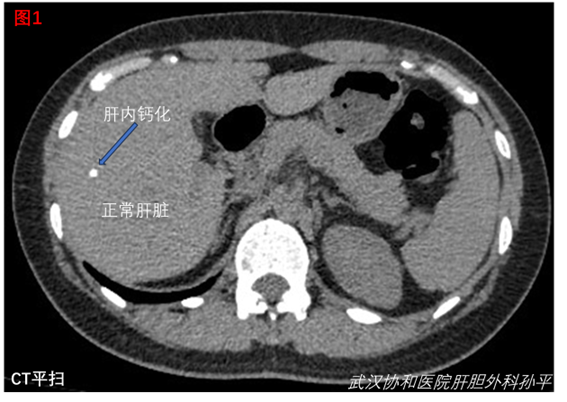

我們科的門診,除了膽囊結(jié)石和膽囊息肉,就屬于肝內(nèi)結(jié)石或鈣化的患者最多。這本身是兩個(gè)問題,肝內(nèi)結(jié)石指肝內(nèi)膽管結(jié)石,石頭在膽管內(nèi),而肝內(nèi)鈣化則在膽管外的肝實(shí)質(zhì),大多數(shù)時(shí)候彩超和CT(圖1)無法分辨是否在膽管內(nèi),故籠統(tǒng)的報(bào)肝內(nèi)結(jié)石或鈣化(見圖2,模式圖)。不管如何,只要檢查沒有明確是膽管內(nèi)結(jié)石,醫(yī)學(xué)界都是建議觀察為主,因?yàn)闊o法分辨即表示石頭不在主要的膽管里面,對(duì)人體并沒有影響,即不會(huì)有不舒服的表現(xiàn),也不會(huì)導(dǎo)致嚴(yán)重的后果。而肝內(nèi)鈣化,醫(yī)學(xué)界認(rèn)為更無關(guān)緊要,因?yàn)楦蝺?nèi)膽管結(jié)石還有可能越長(zhǎng)越多,最終累及主要膽管,需要治療。而鈣化根本沒有這個(gè)風(fēng)險(xiǎn),所以更不會(huì)有不適和不良后果。因此,這兩個(gè)問題目前等同于是同一個(gè)問題,都不需要處理,觀察即可,每年復(fù)查彩超。有人可能擔(dān)心繼發(fā)感染、癌變等風(fēng)險(xiǎn)。誠然,如果明確結(jié)石是在主要的膽管,容易繼發(fā)膽道梗阻、黃疸、反復(fù)發(fā)炎。而慢性炎癥可能誘發(fā)癌變,醫(yī)生都會(huì)建議治療。但癌變是個(gè)漫長(zhǎng)的過程,如果平時(shí)沒有任何癥狀,說明并沒有慢性炎癥的表現(xiàn),癌變的風(fēng)險(xiǎn)和正常人(沒有結(jié)石或鈣化)沒有太大差別。再者,取石都是從肝外的膽管進(jìn)入,用膽道鏡取石,而最細(xì)的膽道鏡也無法進(jìn)入末梢的膽管(圖3),因此,要處理末梢的肝內(nèi)結(jié)石或鈣化,只能切除相應(yīng)部位的肝臟,或者將肝臟剖開慢慢尋找,而肝創(chuàng)面都鮮血淋淋,類似大海撈針??偠灾?,隨訪無風(fēng)險(xiǎn),處理又代價(jià)太大,因此,目前最好的建議是觀察。但觀察不等于不管,需要每年復(fù)查肝膽彩超,了解病情變化,萬一病情進(jìn)展,可以及時(shí)治療。打個(gè)比方,人體就像整個(gè)地球,末梢的小膽管就像每一座山下的小溪,最終越匯越寬,變成大江大河,即為左右肝管和膽總管,最終流向腸道(大海)幫助消化食物。對(duì)于整個(gè)地球而言,一兩條小溪即使廢用,也不影響整體。我們要做的是監(jiān)測(cè)好廢用的小溪,保護(hù)好整個(gè)地球的生態(tài)。每個(gè)患者均有特殊性,具體治療指征和治療方式請(qǐng)咨詢??漆t(yī)生。歡迎轉(zhuǎn)發(fā)給有需要的親人朋友。